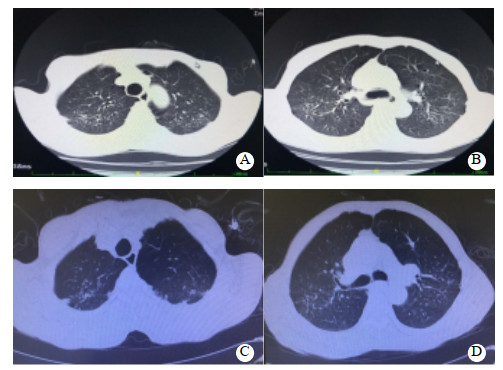

1 资料与方法患者66岁,男性,农民,2020年6月15日下午饮酒(量不详)后误服“虫螨腈”30~50 mL,后昏睡不醒,次日醒酒后出现恶心、呕吐非咖啡渣样胃内容物1次,腹泻3次,为稀水样便,总量少,伴心悸、气促、出汗,无胸闷、胸痛、腹痛,无发热、肌肉酸痛、肌颤、抽搐,家属急送双柏县人民医院急诊科就诊。既往体健,无高血压、糖尿病、心脏病、肺部疾病、外伤等病史。查体:体温36.5℃,心率86次/min,呼吸20次/min,血压102/67 mmHg(1 mmHg=0.133 kPa),血氧饱和度95%(未吸氧);GCS评分15分;全身皮肤出汗,双侧瞳孔等大等圆,直径2.5 mm,光反射灵敏;口唇无发绀;颈软无抵抗,两肺呼吸音清晰,未闻及干湿性啰音;心律齐,未闻及杂音;腹平软,无肌紧张,无压痛及反跳痛,肝脾未触及,肠鸣音正常;双下肢无浮肿,四肢肌力、肌张力正常,病理征未引出。入院后予急诊留观处理,予“奥美拉唑、果糖二磷酸钠、环磷腺苷葡胺、维生素C、维生素B6、氯化钾”静滴及补液对症治疗。心电图示窦性心律,ST-T正常。相关辅助检查见表 1。患者治疗第2天,腹泻缓解,无呕吐发生,正常进食,小便正常。治疗3 d后(6月19日)患者心悸、气促加重,伴大量出汗,收住ICU治疗。查体:体温36.7℃,心率117次/min,呼吸21次/min,血压107/66 mmHg,血氧饱和度95%(鼻导管吸氧3 L/min);GCS评分15分;全身皮肤出汗较多,余无特殊改变。心电图示窦性心律,偶发房性期前收缩,T波低平,见图 1A。肺CT示双肺多发纤维增殖灶,慢性支气管炎,肺气肿,双肺多发肺大疱,见图 2A~B。入住ICU后的相关辅助检查见表 1。继续予上述治疗,并予“地塞米松磷酸钠注射液10 mg/d”静脉注射。经治疗,患者心悸、气促无明显缓解,仍有大量出汗,6月22日转至本院急诊科进一步诊治。查体:体温37.2 ℃,脉搏94次/min,呼吸27次/min,血压103/58 mmHg,血氧饱和度94%(鼻导管吸氧3 L/min);GCS评分15分;全身大汗淋漓,全身皮肤黏膜完好,无破溃,双侧瞳孔等大等圆,直径2.5 mm, 光反射灵敏;口唇无发绀;呼吸急促,心肺腹查体无异常;四肢肌肉无挤压痛,四肢肌力、肌张力正常,病理征未引出。心电图示窦性心律,T波低平,见图 1B。测随机血糖为5.9 mmol/L。肺CT与前相仿,见图 2C~D。相关辅助检查见表 1。本病例资料报道已获得患者家属的知情同意。

| A、B:中毒第5天;C、D:中毒第8天 图 2 患者肺CT结果(示双肺多发纤维增殖灶,慢性支气管炎,肺气肿,双肺多发肺大疱) |